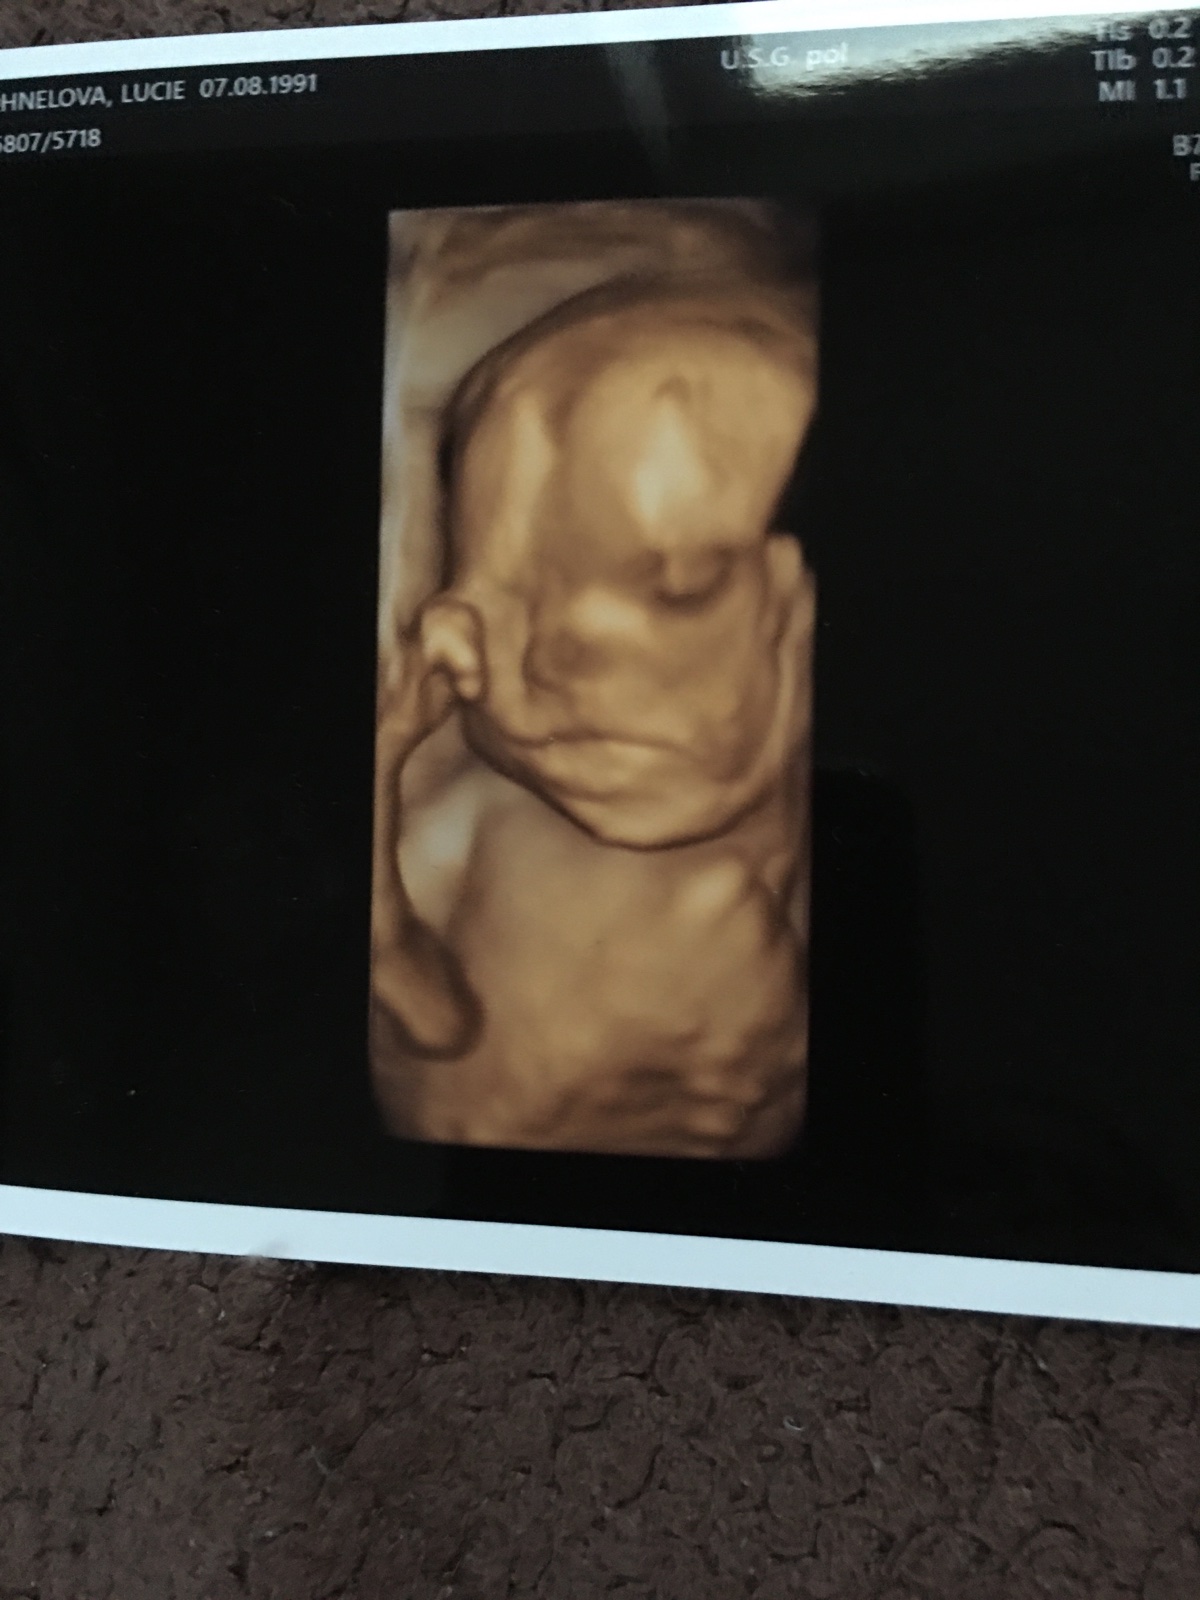

Ahojky, tak se hlásím po dlouhé době. Dnes 26+1 jsem byla na testech na těhotenskou cukrovku a dalo se to v klidu zvládnout ( zítra výsledky ... snad bude vše v pořádku). V 1 trimestru mne zlobil hematom, ve druhém pro změnu polyp, ale už to beru jako samozřejmost 🙂. Čekáme chlapečka. Už ho pěkně cítím já i manžel, i když mám placentu uloženou na přední straně. Asi dva dny zpět mne začala pálit žáha na kterou mi naštěstí zabírá Rennie. Výbavička se mi pomalu ale jistě kupí na balkóně ... už jen postýlka a vymalování ložnice chybí 🙂 🙂

@snazilka3 ahoj, to je paráda 😊 ja jsem dnes 23+0 a v 18tt jsem byla na plodovce, kde vyšlo naštěstí vsehcno v pořádku jen ma maly vadu jako já.. Je přenašeč a ma balancovanou aberaci... Asi týden po plodovce jsem byla v nemocnici, protože mam problémy s pupikem, které jsem měla už dříve, takže teď je to mnohem horší, jak všechno roste a roztahuje se, takže někdy umíram bolesti.. Musím si stále dávat pozor na každý pohyb, nesmím zatinat břicho, dělat prudké pohyby, předklanet se, a příště se pupiku nesmím ani dotknout, jinak mi to hned začne.. Nevím, co to jena ani doktoři.. Pry může být něco v břiše, jako třeba srusty nebo tak něco.. Takže nemůžu ani ns procházku, protože jdu kousek a uz to bolí, jsem z toho špatná, chteka jsem být v těhotenství aktivní a nemůžu. Takže mam strach z každého dne, jak mi poroste bříško, tak to bude určitě horší a horší, jenže když mi to začne, tak se ta bolest nedá vydržet ale prý se nic jiného dělat nedá.. Takže ani nevím, jak porodim, když nemůžu ani na wc tlačit.. Jinak jsou i jiné problémy 🤣 pálení záhy, hemeroidy, bolest zad a kyčli, bolavé a krvácení dásní, 7 kilo nahoře, velká a bolavá prsa.. Std atd.. Bych tu byla do zítra.. Takže sice jsem šťastná, ze čekám nase vymodlene miminko ale těhotenství si opravdu neužívám, uz se těším, až tu bude konecne s námi 😊😊 také čekám chlapečka a placenta vepředu a pohyby od 18tt..od 20tt pravidelně a cítí i přítel, kope jako blázen, ze se hýbe celé břicho a večer me nenechá spát, takže se opravdu někdy nevyspim.. No jsem zvědavá, co bude dál 😀😀. Vybavicku také pomalu a jistě chystám.. Nejprve se chystá pokojíček ale plno věcí už mám... Tak hodně štěstí 🍀

Ahoj, ja začínám 34tt a čekáme chlapečka 💙... Otěhotněla jsem v červenci z druhého KET... Poslední kontorla ve 32+5a maly ma pry moc velké bříško, mam vynechat sladké. Mam o nej strach ale jinak by mělo byt všechno v pořádku. Termín mám 9.4 a uz bych ráda, aby to bylo 😀